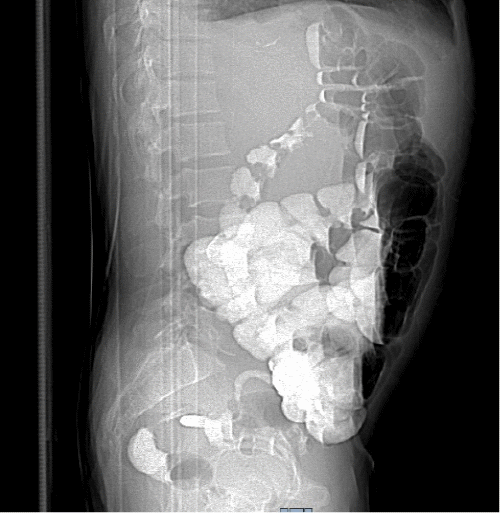

On physical examination, his vitals were within normal limits. He was very thin and had diffuse palpable lymphadenopathy in the cervical and inguinal regions and a large mobile left cheek mass. His abdominal exam was benign, with no anterior abdominal pain but rather bilateral flank pain. The patient's leukocytosis was 13,000 k/cm2, with the remainder of his labs within normal limits; the cluster of differentiation 4 (CD4) count was 2670, and the viral load was 1,391,823. HTLV-I/HTLV-II antibodies were positive. A CT of the abdomen and pelvis with oral and intravenous (IV) contrast was obtained, showing acute tip appendicitis (Figure 1) and extensive bulky gastrohepatic, periportal, peripancreatic, retroperitoneal/para-aortic, bilateral iliac chain, and bilateral inguinal lymphadenopathy (LAD) (Figure 2) with mild splenomegaly suggestive of lymphoma. A CT maxillofacial scan to evaluate his cheek mass also demonstrated extensive bulky cervical lymphadenopathy as well as an enlarged mandibular mass (Figure 3). Of note, the patient had a CT scan performed one year prior that showed an appendix with the same diameter but no local inflammation (Figure 4).

Figure 4. CT Scan: Appendix on CT Scan One Year Prior to Presentation. Published with Permission